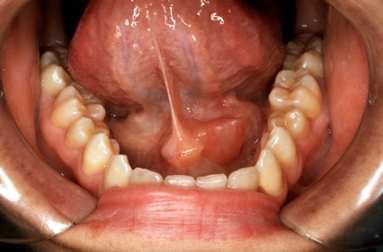

- 입안에서 고름이 나오거나 불쾌한 냄새/맛이 느껴짐

③ 타석증(침샘 결석)

침샘관 안에 돌(타석)이 생겨 침이 제대로 배출되지 않으면 반복적인 염증을 초래합니다. 타석 크기에 따라 저절로 배출되기도 하지만, 크거나 만성적인 경우 내시경적 제거 또는 수술이 필요할 수 있습니다.